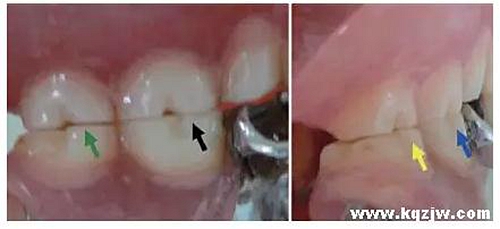

這種咬合接觸的結(jié)果是局部的咬合力集中在凸點接觸的位置,不能被有效分散,可造成受力部位牙體、牙周組織的應(yīng)力集中。最常見的表現(xiàn)是后牙頰舌向呈對刃關(guān)系,另外還常見于不完全遠中關(guān)系或不完全近中關(guān)系的情況,此時從近遠中方向來看,上下后牙牙尖之間凸凸相對(圖3)。

圖3 后牙凸凸接觸關(guān)系